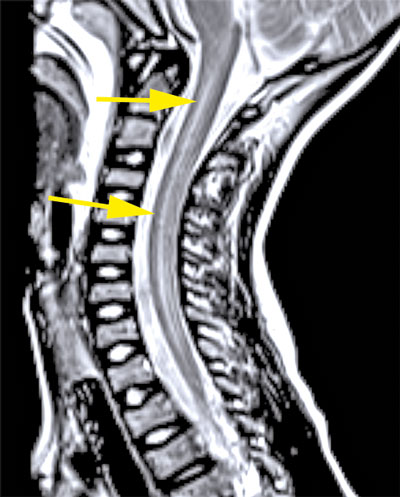

Upprepad MR-undersökning efter drygt 2 veckor visade att signalförändringarna i ryggmärgen hade gått i regress men att det tillkommit kontrastupptag i cervikala och lumbala nervrötter (Figur 2). Neurofysiologiska undersökningar med EnEG, EMG och motoriska reaktionspotentialer 1 månad efter insjuknandet visade tecken på uttalad påverkan av nedre motorneuron i undersökta myotom på vänster sida och en generellt förlängd central överledningstid till undersökta segment på samma sida, vilket talade för påverkan även på centrala motoriska banor.

Figur 2 (fall 2). Vid initial MR-undersökning visade T2-viktad sekvens långsträckta signalförändringar i hela ryggmärgen (första bilden) samt fokalt i bakre delen av pons (andra bilden). Axialt i höjd med C2 påvisades engagerad grå substans (tredje bilden). Vid uppföljande MR-undersökning visade T1-viktad sekvens över halsryggmärgen (sista bilden) endast kontrastladdning i nervrötter.